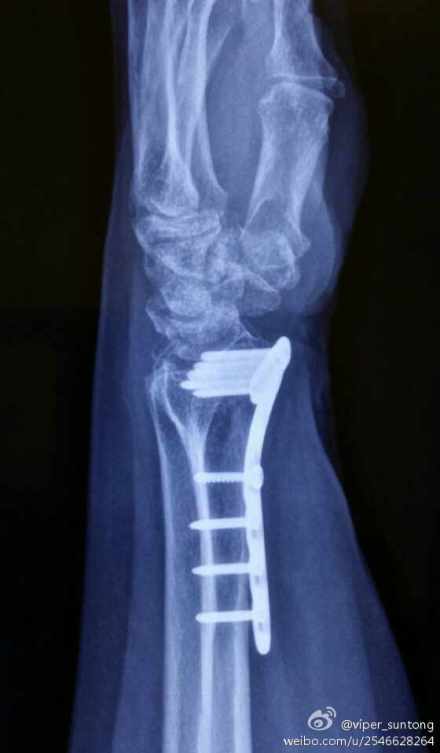

“孙大夫,我又来复查来了!”老太太见到我,兴冲冲地跑了过来,如家人般的亲切。我也赶紧迎上前,招呼她进屋坐下。这是我半年前手术的一个病人,桡骨远端粉碎性骨折。当时的她对手术充满了疑虑与焦虑!患者对手术的恐惧心理与不确定心理,作为一名临床大夫,我是很能体会的。在与她进行了一次长谈之后,她最终还是选择了手术治疗她的骨折。这次来复查,我给她拍了手术部位的X线。术后半年了,桡骨骨折愈合良好,内固定钢板位置也很理想。检查她腕关节的功能,真的很满意(如图)。当我告诉她,她术后的恢复很不错的时候,老太太开心地笑了,向我竖起了大拇指!